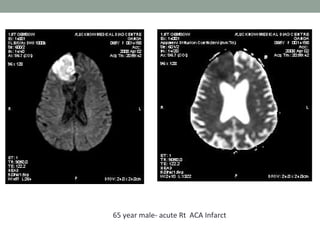

65 year male- acute Rt ACA Infarct

Diffusion-weighted MRI • Diffusion-weightedMRI is a example of endogenous contrast, using the motion of protons to produce signal changes • DWI images is obtained by applying pairs of opposing and balanced magnetic field gradients (but of differing durations and amplitudes) • The primary application of DW MR imaging has been in brain imaging, mainly because of its exquisite sensitivity to early detection of ischemic stroke

• 26.

• The normalmotion of water molecules within living tissues is random (brownian motion). • In acute stroke, there is an alteration of homeostasis • Acute stroke causes excess intracellular water accumulation, or cytotoxic edema, with an overall decreased rate of water molecular diffusion within the affected tissue. • Therefore, areas of cytotoxic edema, in which the motion of water molecules is restricted, appear brighter on diffusion-weighted images because of lesser signal losses

Apparent Diffusion Coefficient •It is a measure of diffusion • Calculated by acquiring two or more images with a different gradient duration and amplitude • The lower ADC measurements seen with early ischemia

• 30.

• The ADCmay be useful for estimating the lesion age and distinguishing acute from subacute DWI lesions. • Acute ischemic lesions can be divided into hyperacute lesions (low ADC and DWI-positive) and subacute lesions (normalized ADC). • Chronic lesions can be differentiated from acute lesions by normalization of ADC and DWI.

65 year male-acute Rt ACA Infarct